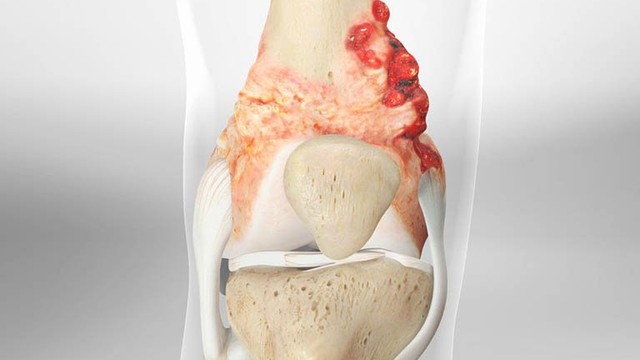

Sarcoma xương là căn bệnh vô cùng nguy hiểm. Nếu mắc phải căn bệnh này mà không được chữa trị kịp thời thì trẻ có thể sẽ phải cắt bỏ chân, tay. Vậy nguyên nhân nào gây ra u xương ác tính?

Sarcoma xương ở trẻ em và thanh thiếu niên là căn bệnh hiếm gặp, nhưng đang dần được trẻ hóa. Trong đó, trẻ em và thanh thiếu niên là hai đối tượng có nguy cơ mắc bệnh cao nhất hiện nay.